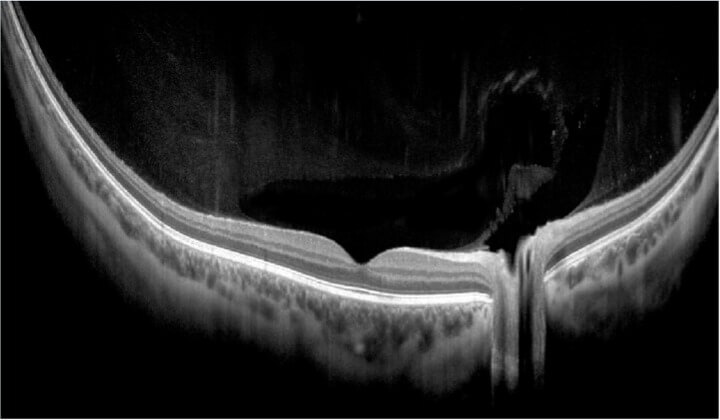

With a unique combination of super-fast scanning at 130,000 scans per second and ultra-high 3μm resolution, this powerful device takes precision, accuracy, and detection of even the finest lesions to a whole new level. The REVO HR is an all-in-one device you can use in a number of ways such as a full colour fundus camera or as a combo, providing simultaneous OCT and fundus images for high quality OCT imaging, including OCT-A.

Wide Retina and Anterior Scans